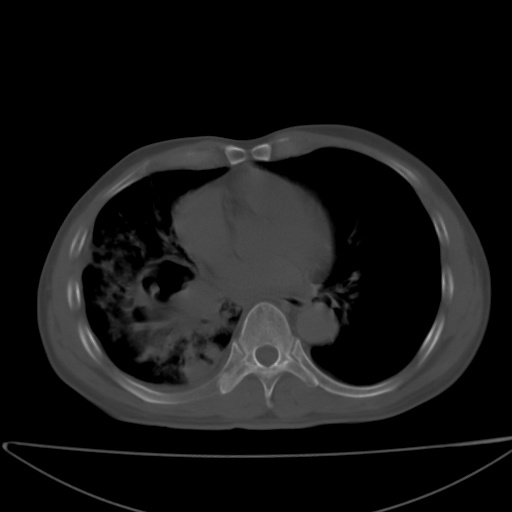

以下是引用jsgdoctor在2008-11-6 22:12:00的发言:[br]右主支气管壁明显增厚,管腔狭窄.考虑为右侧中央型肺癌伴阻塞性炎症\\肺脓肿.

以下是引用zjzjr在2008-11-6 20:25:00的发言:[br]中心型肺ca,合并阻塞性肺炎

以下是引用zsl6918在2008-11-6 19:43:00的发言:[br]右侧中心性肺癌(鳞癌)